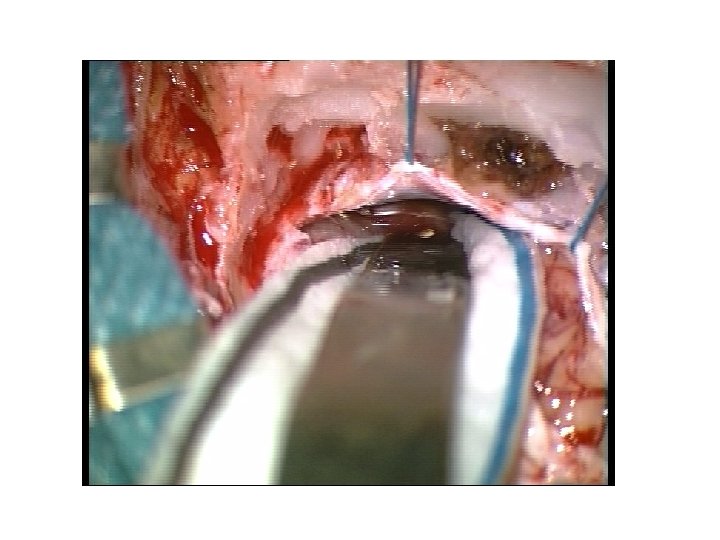

Abord rétro sigmoïde • Dissection arachnoïdienne • Aspiration endotumorale • Fraisage du CAI • Ablation tumeur endocanalaire • fermeture

Abord rétro sigmoïde • Dissection arachnoïdienne • Aspiration endotumorale • Fraisage du CAI • Ablation tumeur endocanalaire • fermeture

Abord rétro sigmoïde • Dissection arachnoïdienne • Aspiration endotumorale • Fraisage du CAI • Ablation tumeur endocanalaire • fermeture

Abord rétro sigmoïde • Dissection arachnoïdienne • Aspiration endotumorale • Fraisage du CAI • Ablation tumeur endocanalaire • fermeture